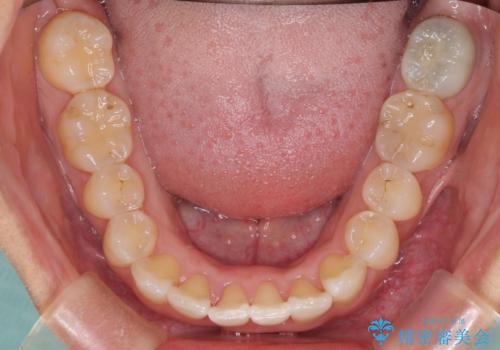

前歯のデコボコをインビザラインでスッキリと仕上げる

- 上下前歯のデコボコと奥歯の銀歯を気にして来院された患者様です。

口元をインビザラインにより歯列を整え、その後に失活している奥歯をオールセラミッククラウンにて補綴治療することとしました。

長時間のマウスピース装着に協力いただき、自然な口元に仕上げることができました。

気になっていた銀歯もオールセラミッククラウンで本物の歯のようになり、患者様には大変満足していただきました。